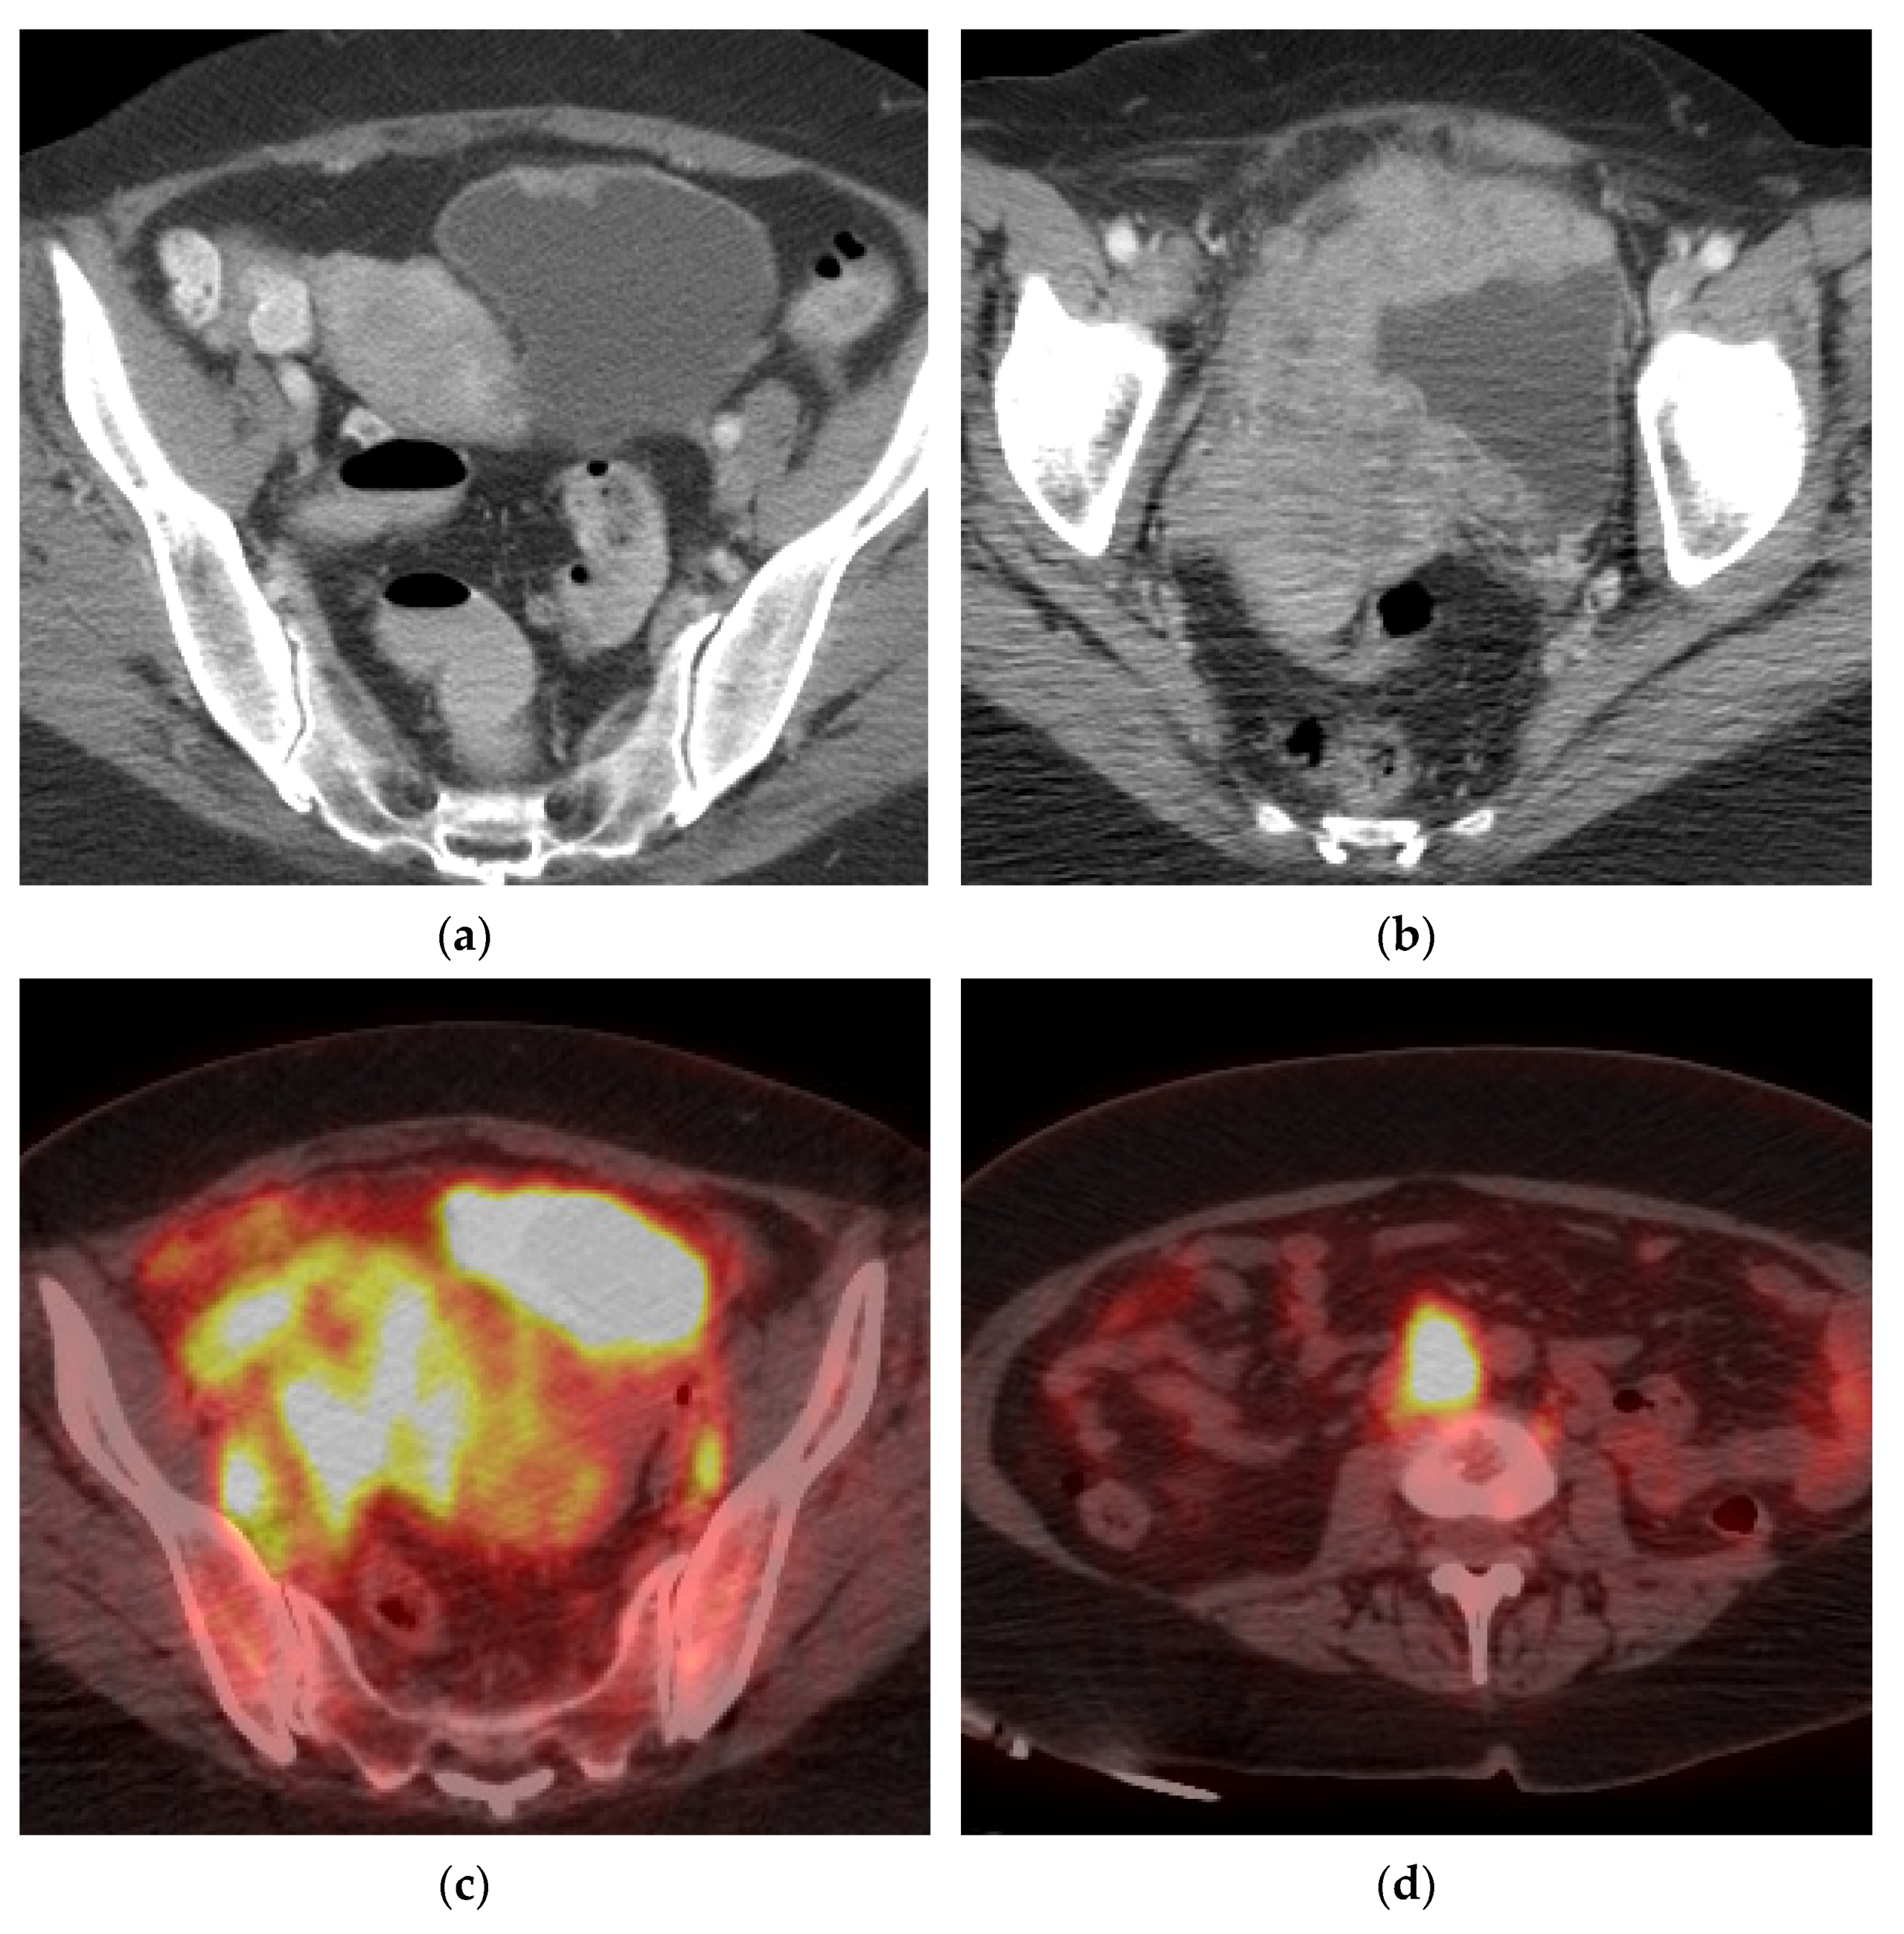

We describe the radiologic findings in six patients with pathologically proved diverticular carcinomas. Between 1986 and 2001 39 patients were treated for tumors in a bladder diverticulum. Within a large right posterior bladder diverticulum there is a round mucosally-based lesion in keeping with a TCC.

The staging system most often used for bladder cancer is the American Joint Committee on Cancer AJCC TNM system which is based on 3 key pieces of information. The posterior wall of the lesion abuts the external iliac vessels with loss of the intervening fat plane Image 32. Recurrence is higher as you go from A to D but again this is a percentage and does not happen to everyone.